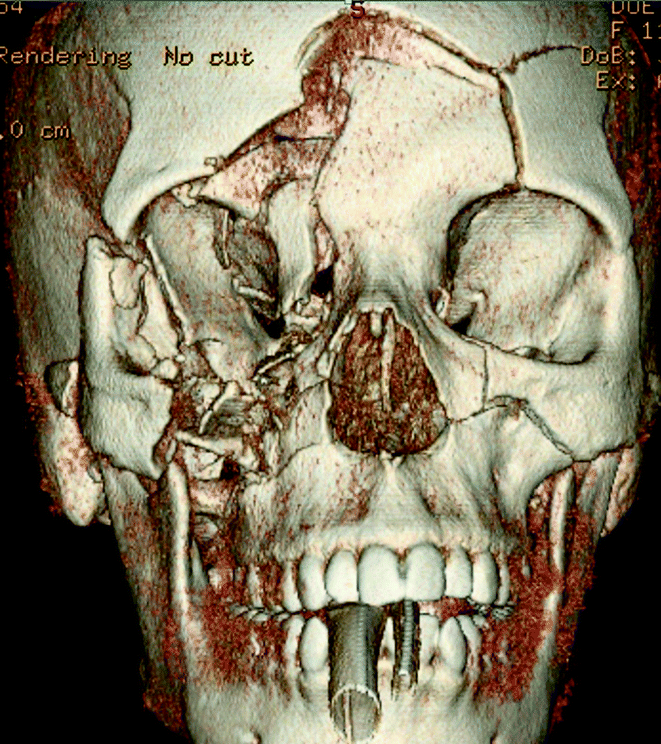

Fig. 19.6

Initial head CT demonstrating comminuted fractures of the frontal, temporal, and parietal bones, metallic fragmentation, traumatic subarachnoid hemorrhage around the anterior falx, and extensive soft tissue hemorrhage

A 27-year-old male deployed overseas suffered a gunshot wound to the head from an unknown caliber weapon. He underwent an emergent cricothyroidostomy and was transferred to higher level care with an admission GCS score of 8T. Initial head CT demonstrated significant right maxillary, orbital, frontal, and zygomatic fractures, retained metal fragmentation within the right frontal lobe and effacement of the frontal horn of the right lateral ventricle. A left frontal EVD was placed but within 24 h his ICPs were refractory to medical management. He underwent a right unilateral craniectomy in theater. He was transferred back to Walter Reed for further care and rehabilitation. One month after the accident he was discharged to neuro-rehab with a GCS 14 and moderate impairment in judgment and insight. He underwent cranioplasty 6 months after the injury.